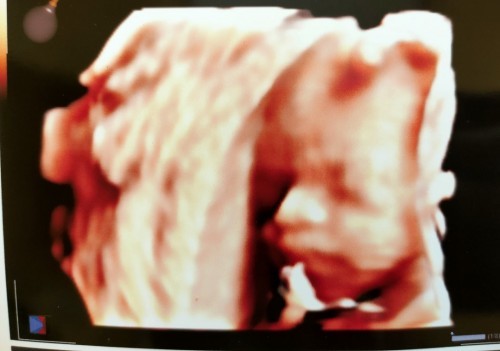

Hi Mom.. saya saat ini 37 w lewat 5 hari, udah 5 hari ini saya pembukaan 2 yang di sertai flek,lendir, perut mengencang, sakit pinggang dan tanpa mules.. hampir setiap hari di PD rasanya ngilu banget, ke dokter atau bidan pasti di suruh pulang. Rutin olah raga hamil, jalan kaki kecuali hb (suami ga tega katanya karena ada flek dan udah nyeri). Mules ga juga hadir. Anehnya tadi di PD (periksa dalam) sama bidan yang lain katanya pembukaan saya mengecil jadi pembukaan 1. Saya mau tanya mom's ada yang pernah ngalamin kaya saya ga? Terus solusinya gmna? #seriusnanya #bantusharing #pleasehelp